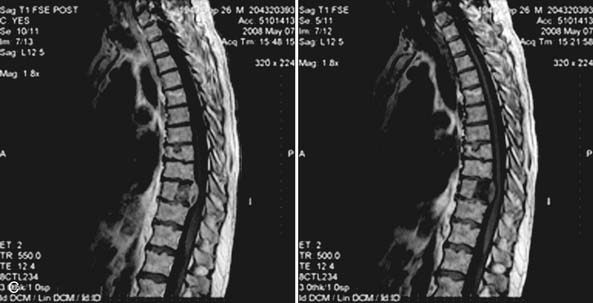

Primary Osseous Malignancies of the Spine。Thoracic spine metastases from lung cancer with incomplete。Frontiers | Stevens–Johnson syndrome induced by toripalimab。「WHO Classification of Tumours, 5th ed., Vol.5」著者: WHO Classification of Tumours Editorial Board出版社: WORLD HEALTH ORGANIZATIONISBN: 978-92-832-4506-3ページ数: 565pp.出版年: 2021年定価 :23.550円(税抜)裁断済みです。診察ができる vol.1 身体診察。Risk Factors for Poor Outcome after Palliative Surgery for。汚れはありません。